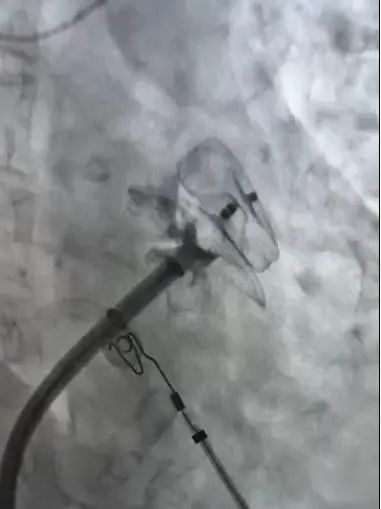

微信圖片_20250414082739

釋放后的左心耳封堵器

手術(shù)在西安交通大學(xué)第二附屬醫(yī)院王洪濤教授的指導(dǎo)、何麗團(tuán)隊(duì)及超聲科羅利紅主任團(tuán)隊(duì)、相關(guān)科室的配合下開展。在確認(rèn)患者心耳內(nèi)無血栓的情況下,手術(shù)團(tuán)隊(duì)結(jié)合食道超聲和CTPV術(shù)前結(jié)果,在完成環(huán)肺靜脈隔離后,選擇合適左心耳封堵器,一次展開即完成封堵,兩種術(shù)式實(shí)現(xiàn)無縫銜接,手術(shù)用時(shí)約2個(gè)鐘頭。在醫(yī)務(wù)人員的精心照護(hù)下,患者目前恢復(fù)良好。